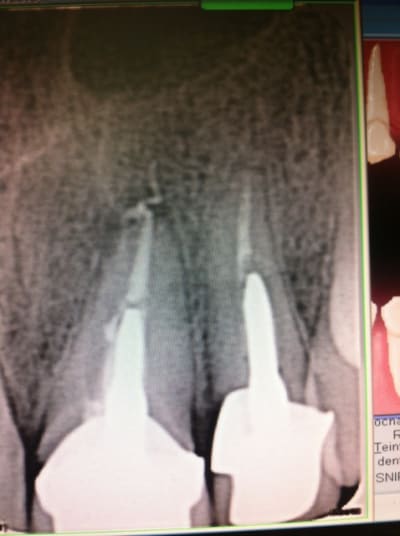

Patient venant en urgence avec bel abcès palatin entre 21 et 22.

Ras à la rétro sauf un petit dépassement sur 21. Gencive tuméfiée, violacée en vestibulaire de 21-22. La 21 a déjà eu un Rte il y a 4 ans.

Rien au sondage, mais en regardant de plus prés la rétro, je suspecte un trait de fracture en distal de 22...

Mis sous Antibio, plus de signe clinique. Prescription de cone Beam et surprise, belle image...